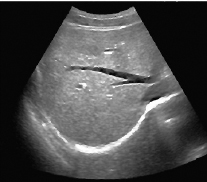

Примеры изображений:

Визуализация печени, В-режим

Визуализация печени, В-режим